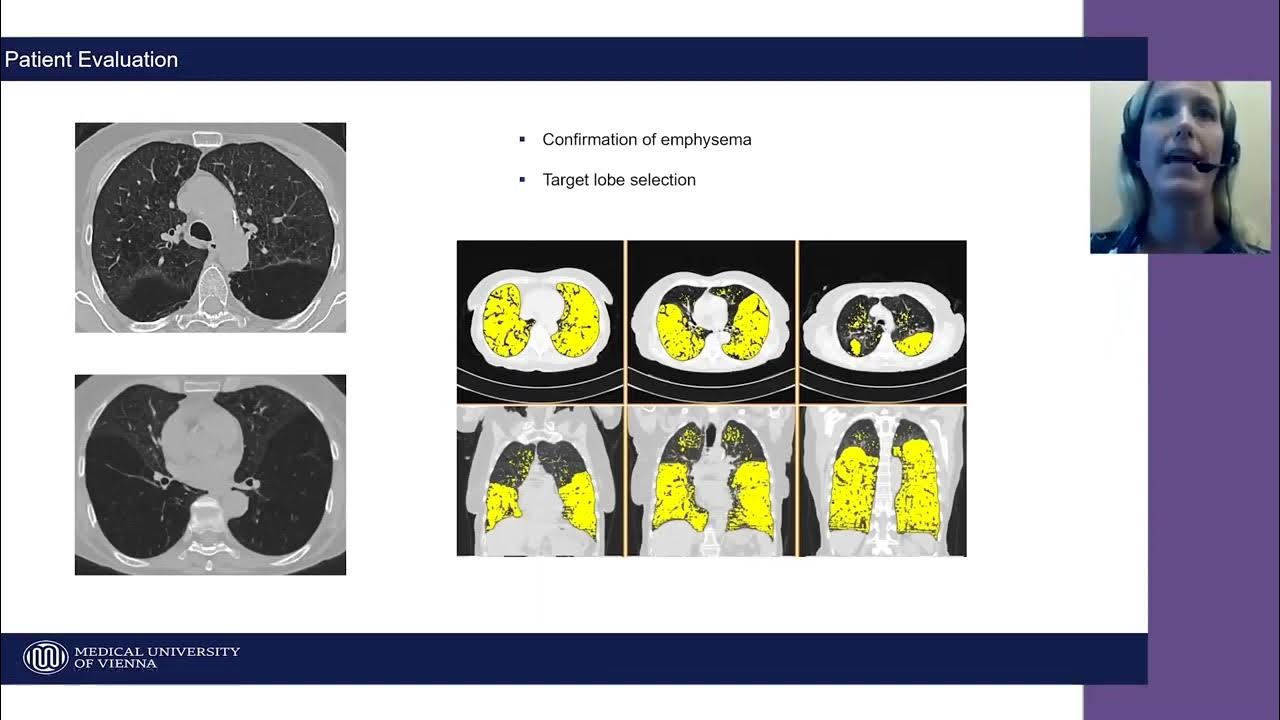

Emphysema, a form of chronic obstructive pulmonary disease (COPD), progressively damages the air sacs (alveoli) in the lungs. This damage leads to hyperinflation, where air gets trapped in the lungs, making it difficult to breathe. The trapped air compresses healthier regions of the lungs, hindering their ability to function efficiently.

The Zephyr Valve works by blocking airflow to the most diseased parts of the lung, allowing the healthier regions to expand and function better. These tiny one-way valves are placed in the airways during a bronchoscopy, a minimally invasive procedure.

Pulmonary function tests, such as spirometry, help track changes in lung function over time. Imaging studies, like chest X-rays or CT scans, can help visualize the position of the valves and identify any signs of valve migration or other issues.